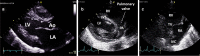

Cardiac ultrasound techniques are increasingly used in the neonatal intensive care unit to guide cardiorespiratory care of the sick newborn. This is the first in a series of eight review articles discussing the current status of "neonatologist-performed echocardiography" (NPE). The aim of this introductory review is to discuss four key elements of NPE. Indications for scanning are summarized to give the neonatologist with echocardiography skills a clear scope of practice. The fundamental physics of ultrasound are explained to allow for image optimization and avoid erroneous conclusions from artifacts. To ensure patient safety during echocardiography recommendations are given to prevent cardiorespiratory instability, hypothermia, infection, and skin lesions. A structured approach to echocardiography, with the same standard views acquired in the same sequence at each scan, is suggested in order to ensure that the neonatologist confirms normal structural anatomy or acquires the necessary images for a pediatric cardiologist to do so when reviewing the scan.